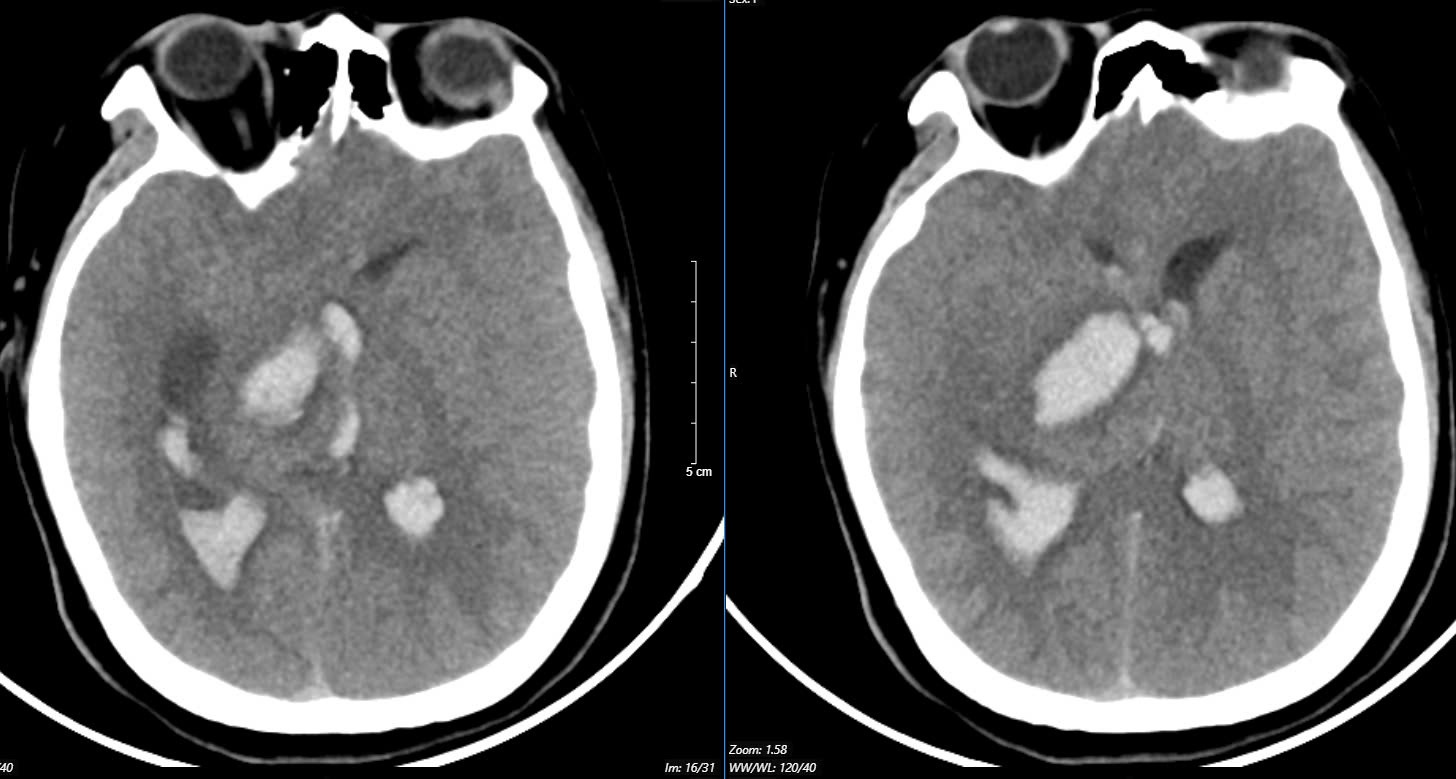

Tại Trung tâm Đột quỵ, Bệnh viện Bạch Mai, bệnh nhân ở trong tình trạng: Ý thức hôn mê sâu, Glasgow 5 điểm, thở máy, giãn đồng tử bên phải. Kết quả chụp lại phim MSCT mạch não chảy máu não đồi thị - não thất do vỡ khối AVM (dị dạng thông động- tĩnh mạch não) biến chứng giãn não thất cấp, rối loạn thân nhiệt, sốt cao liên tục 39 - 40 độ C.

Khối dị dạng mạch não tuy không quá lớn nhưng ở vị trí cực kỳ nguy hiểm. Mặc dù đã được hồi sức tích cực tại Trung tâm Đột Quỵ nhưng tình trạng diễn biến nhanh, bệnh nhân tụt huyết áp, thiểu niệu, rối loạn thân nhiệt, hôn mê sâu Glasgow 3 điểm.

Hình ảnh chụp phim MSCT mạch não chảy máu não đồi thị - não thất do vỡ khối AVM (dị dạng thông động- tĩnh mạch não) bệnh nhân 15 tuổi. Ảnh BVCC